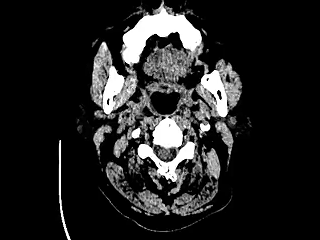

头部CT、胸部CT